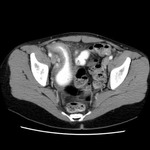

Aneurisma da aorta abdominal: tomografia computadorizada (TC) de um aneurisma da aorta abdominal roto

University of Michigan, mais especificamente os casos do Dr. Upchurch, representando os Departamentos de Cirurgia vascular e Radiologia